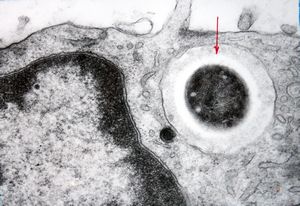

F,52y. | bone marrow - inclusions in plasmocytes

M,62y. | bone marrow - plasmocytoma - inclusions